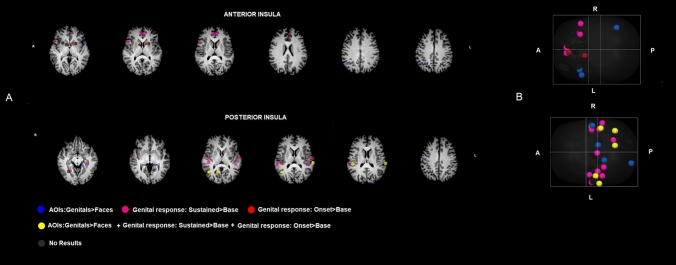

In the posterior insula target regions pattern, for the AOIs comparison (Genital > Faces) significant results have been found for the postcentral gyrus (p < 0.05 Bonf.corr.). Moreover, the right precentral gyrus (p < 0.05), posterior part of the superior temporal sulcus-gyrus/angular gyrus (p < 0.05) and the supramarginal gyrus (p < 0.05), cuneus (p < 0.05), thalamus (p < 0.05), and STG (p < 0.05); left angular ayrus (p < 0.05), posterior insula (p < 0.05) and postcentral gyrus (p < 0.05) all showed significant (but uncorrected significance level). As for genital response, we found significant results for the contrast Onset > Baseline in correspondence right angular (p < 0.05 Bonf. corr) and supramarginal gyrus (p < 0.05 Bonf. corr), cuneus (p < 0.001 Bonf. corr) and STG (p < 0.001 Bonf. Corr). For the Sustained > Baseline significant results have been observed in right angular (p < 0.001 Bonf. corr) and supramarginal gyrus (p < 0.001 Bonf. corr), cuneus (p < 0.001 Bonf. corr), STG (p < 0.001 Bonf. Corr), left supramarginal gyrus (p < 0.001 Bonf. Corr—Fig. 4). More details regarding the analyses and findings are presented in the supplementary materials (Table S1).

Figure 4.

Single-ROI GLMs results. Image depicts the brain regions, spherical ROIs in which the 3 Single-ROI GLMs have been applied of the Anterior Insula Pattern and Posterior Insula Pattern. ROIs have been grouped, using different colors, on the bases of the GLMs results as described in the figure. (A) ROIs are overimposed on a Talairach template, which is in radiological convention (B) the same ROIs are overimposed on a Glass-brain in neurological convention. Brain ROIs have been created by means of TalCoord2VOI Plugin implemented in Brain voyager 2.8.

Interestingly, we observed a predominant effect for the posterior insula over the anterior one. Among the target regions of the anterior insula, few showed a significant relationship with the attentional and genital processes during VSS. Instead, in the target regions of posterior insula we found three different pathways: the first is composed by a set of regions involved in the visual focused attention, onset of the erection and sustained erection; the second is only involved in processes related to the onset of erection; and the third is only related to the maintenance of or sustained erection. Moreover, we observed several regions, including in the pathway, that did not show significant associations with one or more of the three processes.